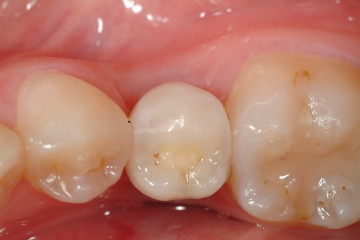

患者許小姐,左下第二小臼齒,因為深度蛀牙,因而牙齒被拔除(圖一、圖二、圖三),患者由於是一位高二學生,深怕缺牙久了若不處理,鄰牙可能倒過來(圖四),但若以傳統假牙修復,還需再磨完整的自然牙(圖五),經轉診至本診所尋求人工植牙。

圖二 |